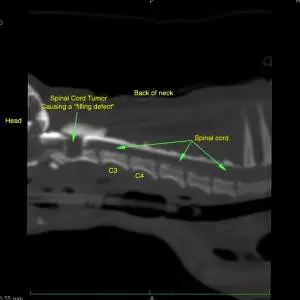

A complete blood count (CBC), chemistry panel, and thoracic radiographs were performed. A CT/myelogram was performed at another hospital and showed an abnormality at C1-C2. Remember, there are three main myelographic patterns:

• Intradural-extramedullary: Inside of the dura, but not inside the spinal cord itself. Contrast in the subarachnoid space flows up to the abnormality, and there may be a ‘filling defect’ within the subarachnoid space. A ‘golf-tee’ sign may be seen.

Note the ‘golf-tee’ sign, which is classic for an intradural-extramedullary mass. Given the severity of her signs, the location of the presumed tumor and her small size, a poor prognosis was given at the first hospital and euthanasia was discussed.

Lupa’s CT/myelogram